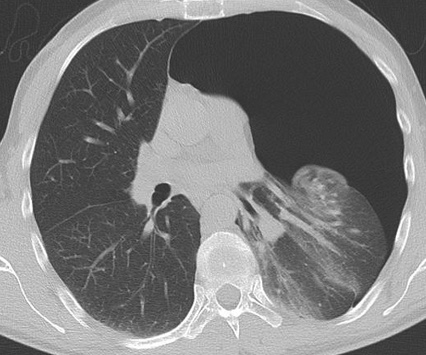

- A risque de Bulles et donc de Pneumothorax